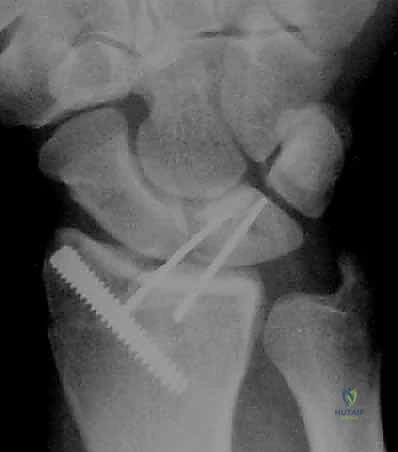

- تشخيص وعلاج الإصابات المصاحبة: أثبتت الدراسات الحديثة أن نسبة كبيرة من كسور الكعبرة تصاحبها تمزقات في أربطة الرسغ أو في المعقد الغضروفي (TFCC). الجراحة المفتوحة قد تغفل هذه الإصابات، بينما يكتشفها المنظار ويعالجها في نفس الوقت.

يتم ضخ سائل معقم لغسل المفصل من الدم المتخثر والفتات العظمي. يقوم الجراح بفحص الغضروف، الأربطة (Scapholunate و Lunotriquetral)، وغضروف الـ TFCC.

الخطوة الرابعة: رد الكسر تحت الرؤية المباشرة

باستخدام أدوات دقيقة، يتم تحريك القطع العظمية المكسورة وإعادتها إلى مكانها الطبيعي. يراقب الجراح العملية عبر شاشة المنظار ليتأكد من أن السطح المفصلي أصبح مستوياً تماماً بنسبة 100%.

بمجرد استعادة الشكل التشريحي، يتم تثبيت العظام. قد يتم استخدام أسلاك كيرشنر (K-wires)، مسامير دقيقة، أو شريحة معدنية داعمة (Volar Plate) توضع من خلال شق صغير منفصل لضمان ثبات الكسر التام. يتم أيضاً خياطة أي تمزق في الأربطة إن وجد.